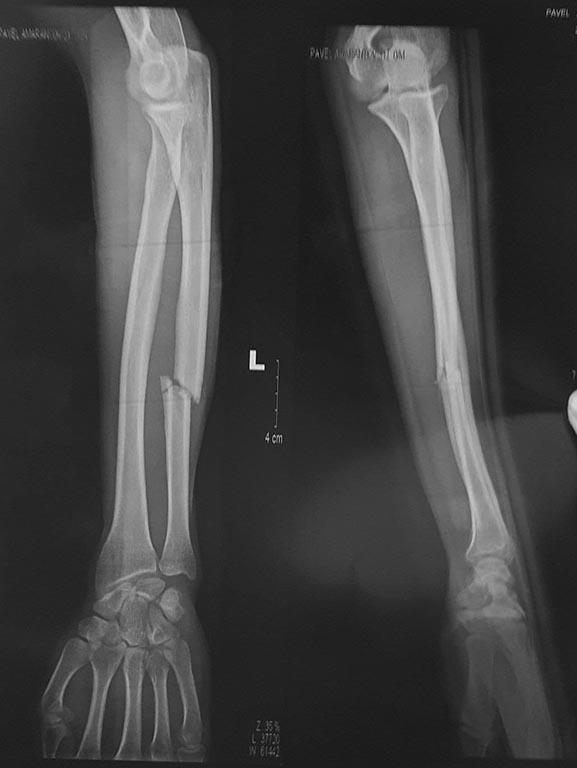

Перелом локтевой кости левой руки со смещением(снимки прилагаю).

Список того, что мы услышали на вопрос о лучшем лечении:

1)ничего не делать, гипса достаточно, срастётся через 2-3 месяца, моторика и функции руки полностью восстановятся через 1 год;

2)нужна операция, надрез и установка пластин, которые потом останутся навсегда,но это не страшно(т.к. если я не сделаю операцию, то не смогу спустя год нормально крутить в стороны сжатым кулаком);

3)нужна операция, надрез и установка металл. скоб, которые потом снимут через 1-2 месяца;

4)нужна операция, с применением биодеградируемых винтов, которые по мере срастания кости сами рассасываются бесследно и без последствий (по срокам не сказали);

5)нужна операция, 6-8 дырок и что-то типа аппарата Илизарова, на 2 месяца, потом аппарат снимают и накладывают открытый гипс ещё на 2 месяца;

Мне важно, чтобы я смог заниматься физкультурой(средние нагрузки), плаванием, скалолазанием после восстановления.